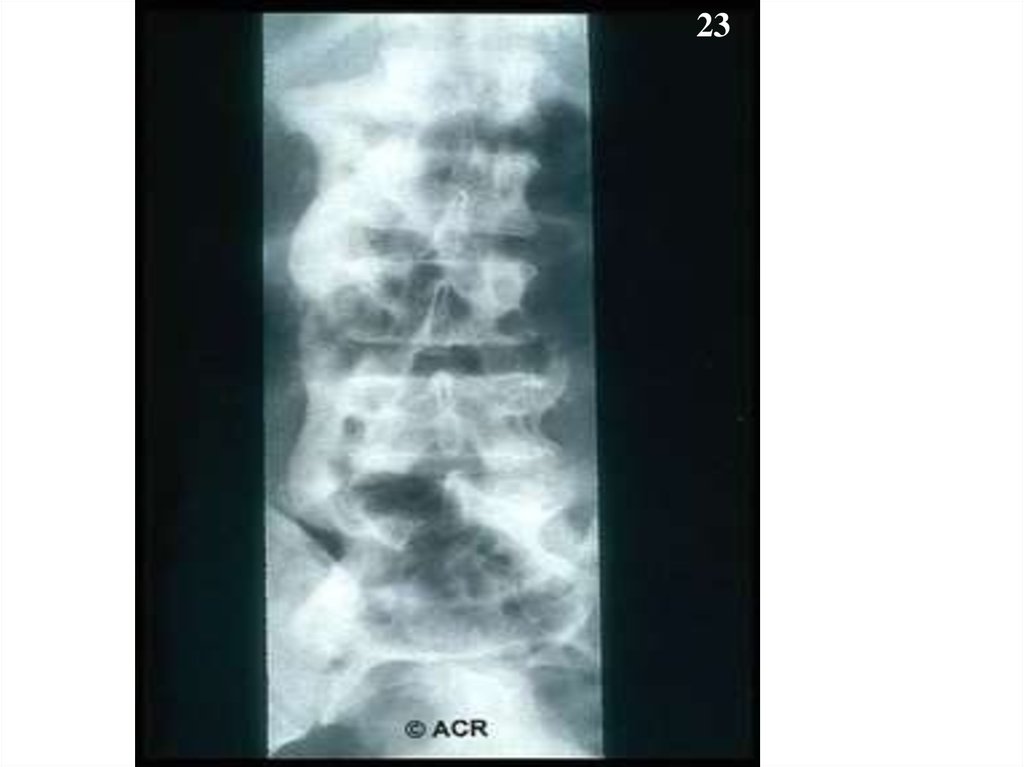

23.

23